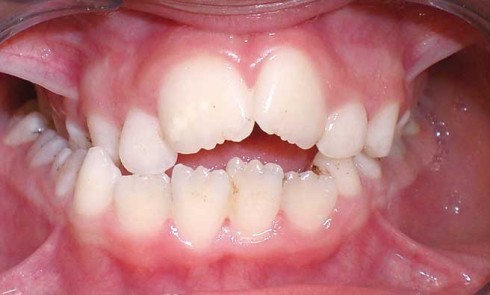

Article réservé à nos abonnés Prise en charge orthodontique précoce : place de l’omnipraticien

La prise en charge d’une malocclusion doit se faire le plus précocement possible. Ceci semble être aujourd’hui un principe partagé...